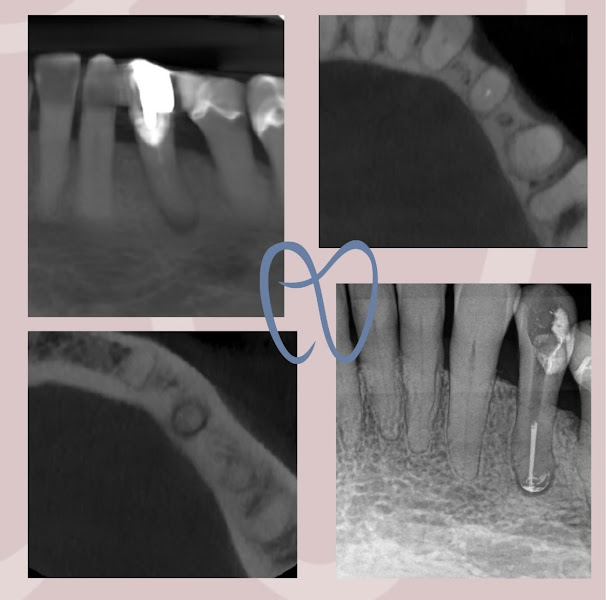

Dra. Maria Tereza Andrade Aragão - Consultório Odontológico - Endodontia / Canal com Microscópio

Fotos